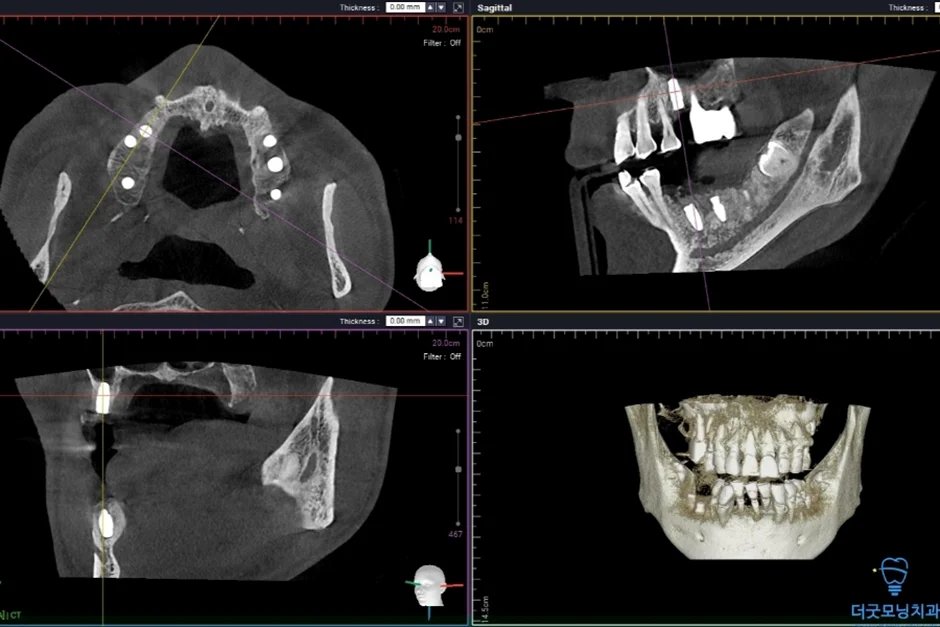

■ 1차 수술 (오른쪽)

미다졸람을 투여 후 편안하게 수면에 드신 상태에서 오른쪽 임플란트 수술을 먼저 진행하였습니다.

아래 임플란트 제거한 사진

임플란트를 치조정 접근 상악동 거상술을 통해 3개의 임플란트가 식립된 사진

하악의 임플란트 주위염 부위는 기존 임플란트를 제거하고 재식립하였으며, 상악의 경우 치조정 접근 상악동 거상술을 통해 3개의 임플란트를 안정적으로 식립하였습니다.